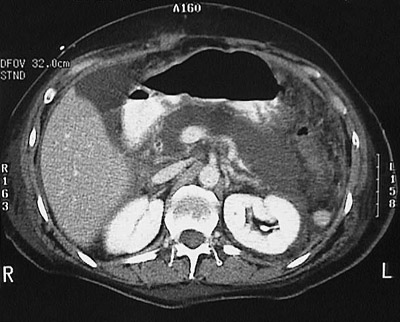

![]() | This computed tomographic (CT) scan with contrast of the abdomen reveals acute pancreatitis with decreased enhancement of the swollen pancreas as a result of the edema, hemorrhage, and fat necrosis. In this case, as a consequence of the inflammation, can be seen a splenic vein thrombosis. |